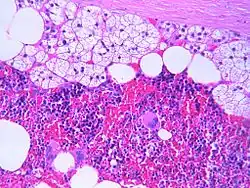

An adrenal myelolipoma

The microscopic view of a myelolipoma shows the presence of normal adrenal cells, fat (adipose) cells, and the three lineages of the myeloid precursors

The typical microscopic features of myelolipomas are shown in the image. There is a mixture of normal adrenal tissue, fat, and a full trilineage maturation of the three major blood-forming elements: myeloid (white blood cell forming), erythroid (red blood cell forming), and megakaryocytic (platelet forming) lines.[1]